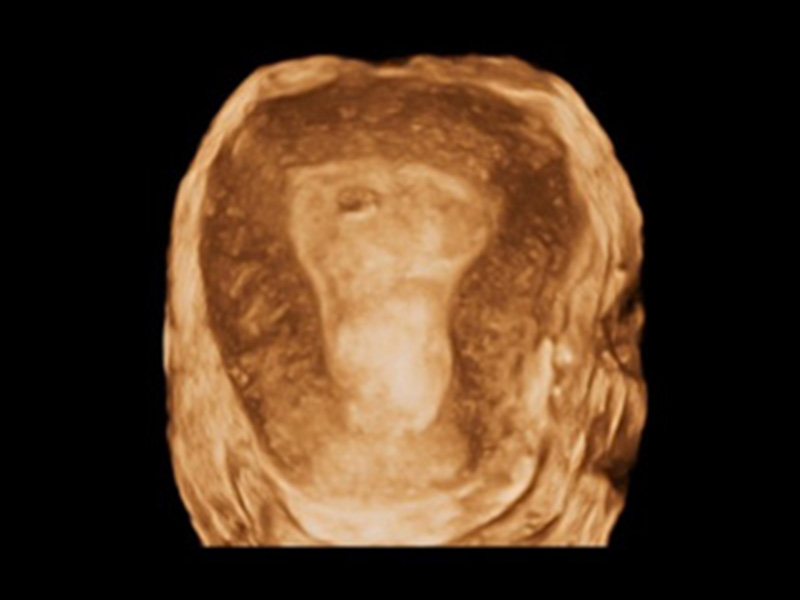

Smart 3D/4D

Der neue High-Density-Volume-Rendering-Engine von P60 Exp optimiert signifikant die Signalverarbeitung und 3D-Rendering, was seine volumetrische Leistung in Bezug auf hohe Volumenraten, außergewöhnliche Details und realistische Effekte hervorhebt. Die umfassende Volumenbildgebungssuite erweitert Ihre diagnostischen Fähigkeiten in die nächste Ära der Bildgebung mit außergewöhnlicher Bildqualität und optimiertem Workflow.

• IUD mit 3D-Rendering

• Fetus im 1. Trimester mit 3D S-Live Silhouette

• Fetale Finger mit 3D S-Live

• Fetaler Rücken mit FreeVue und VCI

• Innere Struktur des Fetus mit S-Live Contour